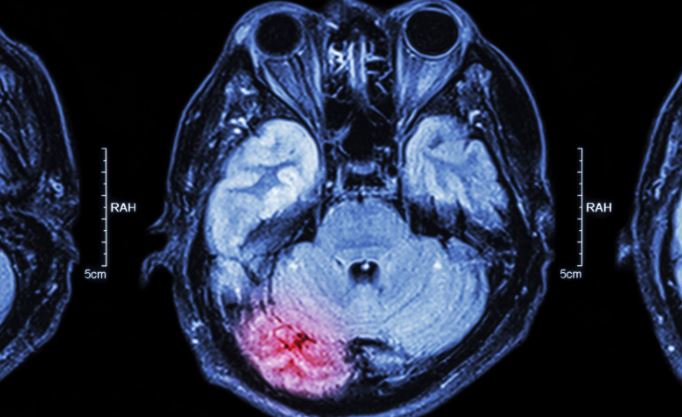

아무튼 뇌졸중은 뇌의 혈관이 좁아지고 해당 혈관에 피가 지속적으로 지나가면서 혈관이 무리를 하여 터져버리는 증상이다. 평균 5시간 이내에 병원에서 치료를 받지 못하면 사망에 이를 수 있는 무시무시한 질병이다.

처음에 위에서 언급했듯이 뇌졸중은 뇌의 혈관이 좁아져서 혈액순환을 원활하게 이루지 못하고 터지는 증상이다, 이러한 상황에서 두통이 없을 수는 없다..

뇌를 주기적으로 정밀검사를 하기 위해서는 MRI 촬영을 정기적으로 받아야 한다, 허나 서민의 입장에서 과연 정기적으로 MRI 검사비용을 감당할 수 있을까?